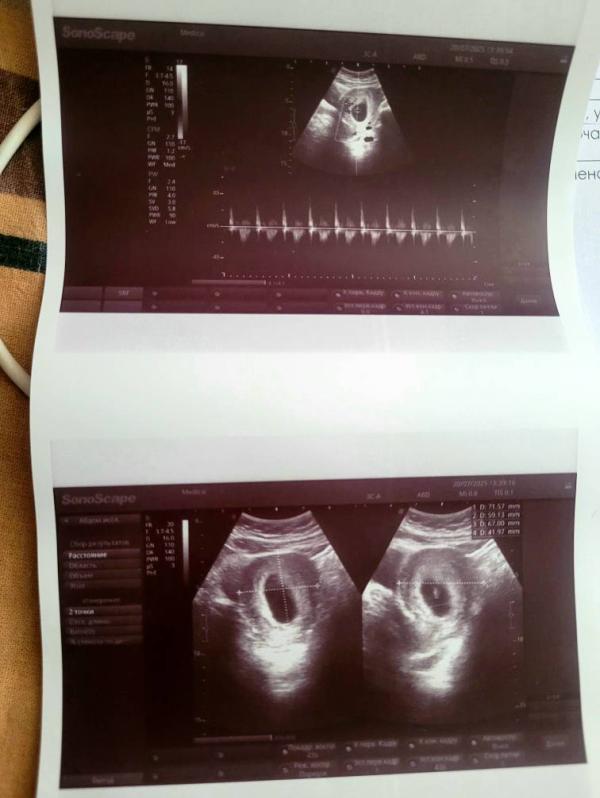

Девочки, сходила на ультразвуковое исследование, очень переживала, дали послушать сердечко, я просто чуть с ума не сошла от счастья, сказали, биометрия соответствует сроку 7,2 недель беременности, но эмбрион все равно очень маленький, но то, что есть сердцебиение, будем считать, что всё хорошо. 🙏 Немного напряглась я, конечно, но думаю, он еще вырастет, он же на таком сроке размером с чернику. 🫐